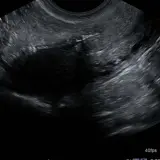

Over 2,100 interactive radiology cases, curated by radiologists for your level of training. Scroll, window, and view cases full screen โ€” just like on PACS. Click linked findings in each writeup to jump straight to them on the image. Cases include sample reports, a focused discussion section, original illustrations, and videos.

Casi completamente interattivi con gli strumenti che ti aspetti su un PACS: scroll, windowing, zoom, pan, misurazioni, ROI e modalitร  a schermo intero.

Annotazioni dettagliate evidenziano i reperti chiave direttamente sui casi. Clicca sui reperti collegati nella descrizione del caso per saltare alla loro esatta posizione sullo scan.